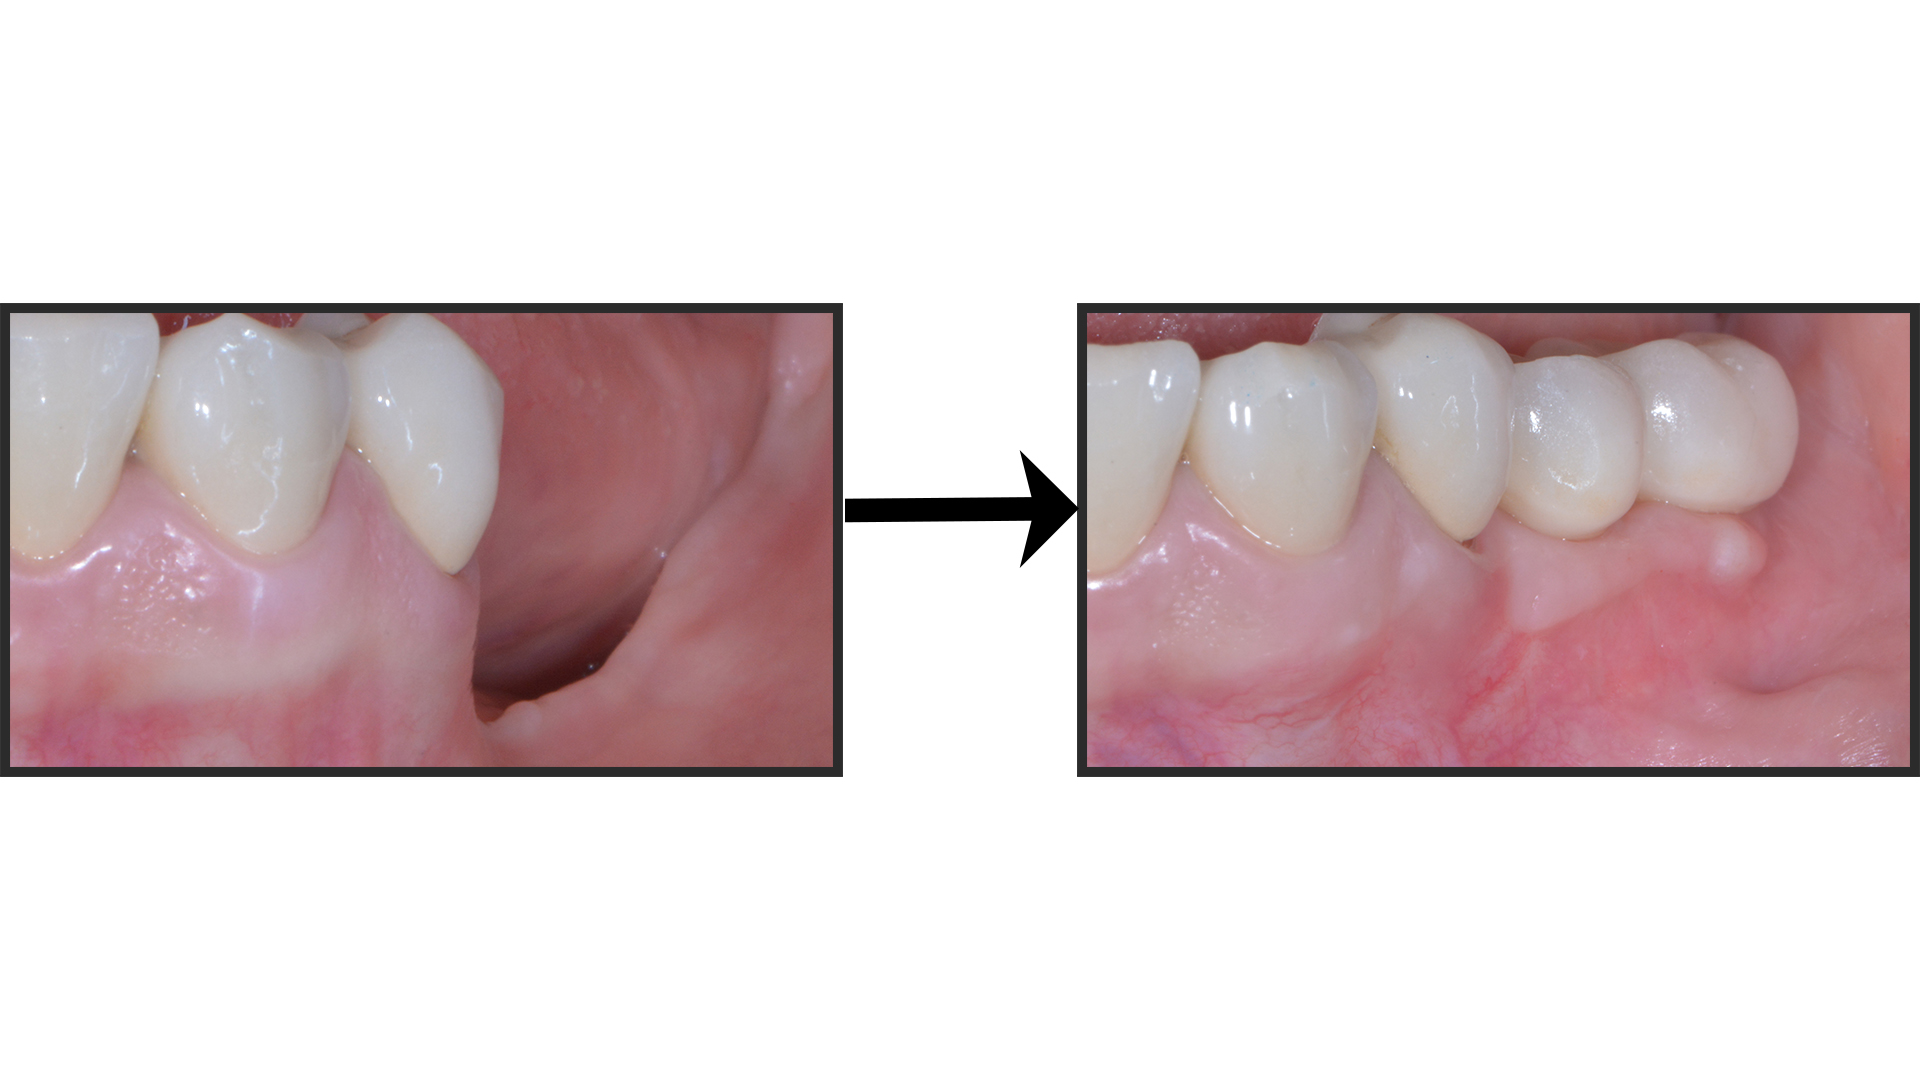

Casi rognosi come questo:

O questo:

O questo: